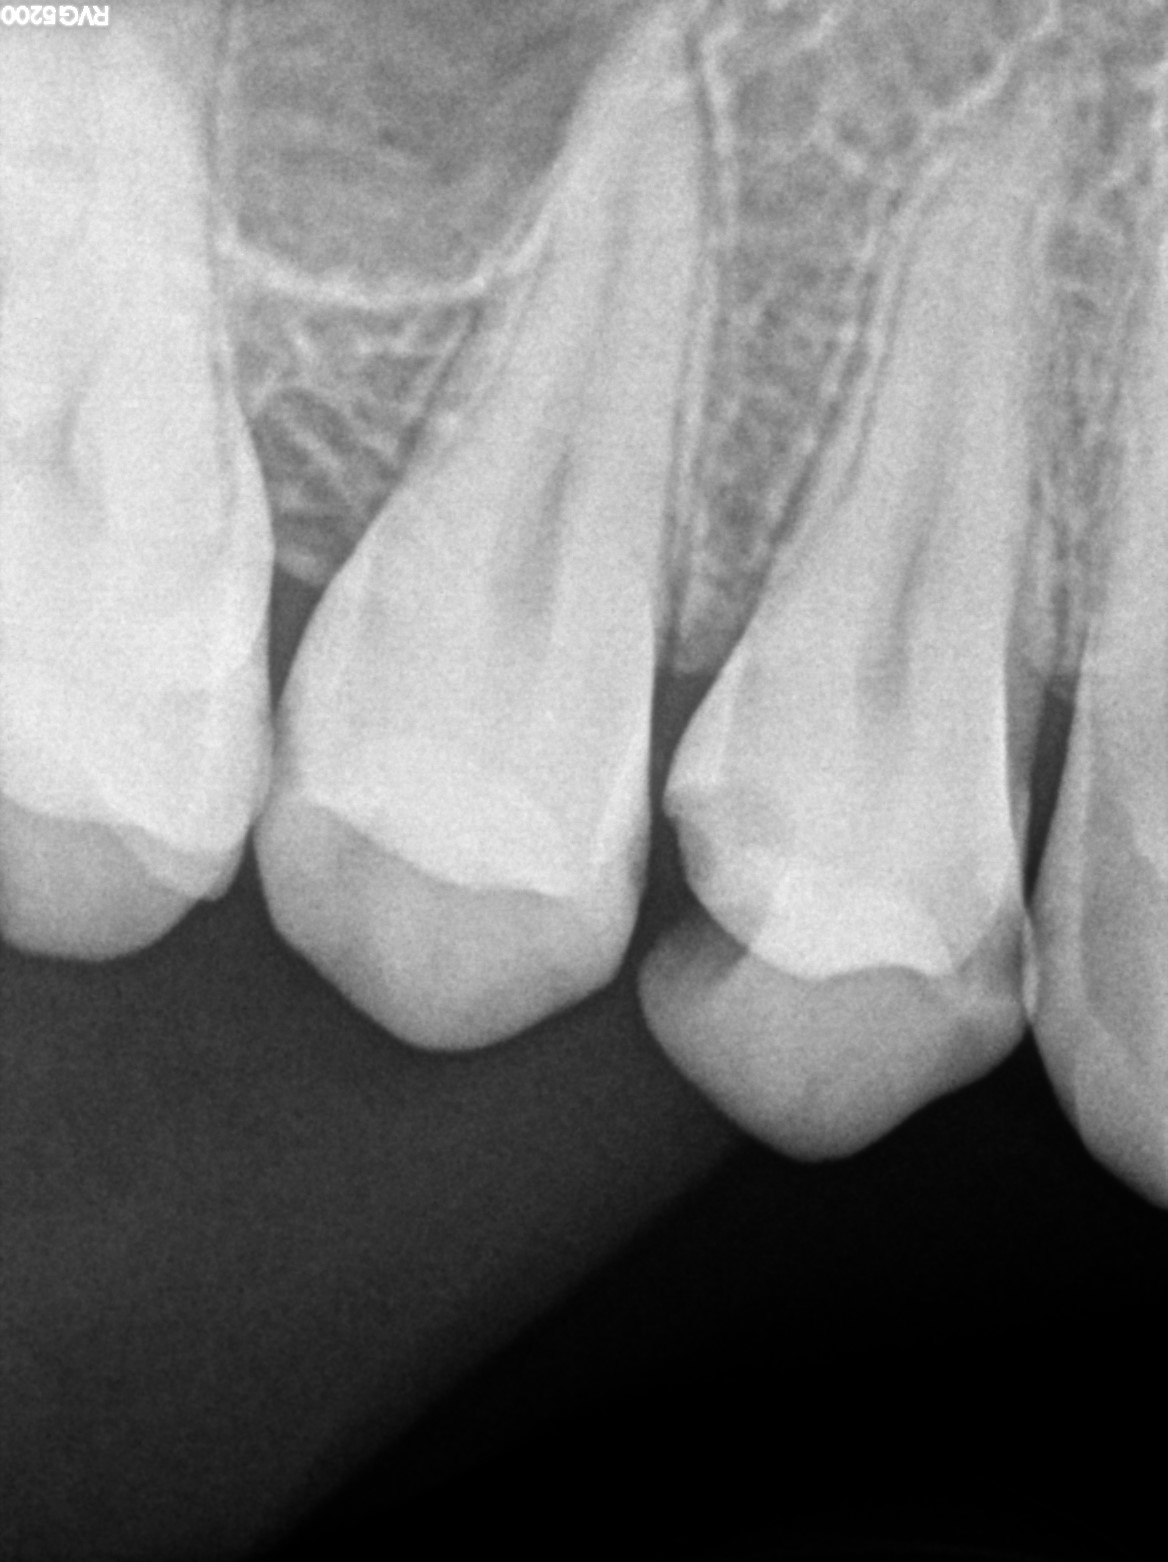

Dental Radiographs FHIR: DocumentReference · LOINC 24641-7

xray_1742370818.jpg

24641-7

xray_1742370851.jpg